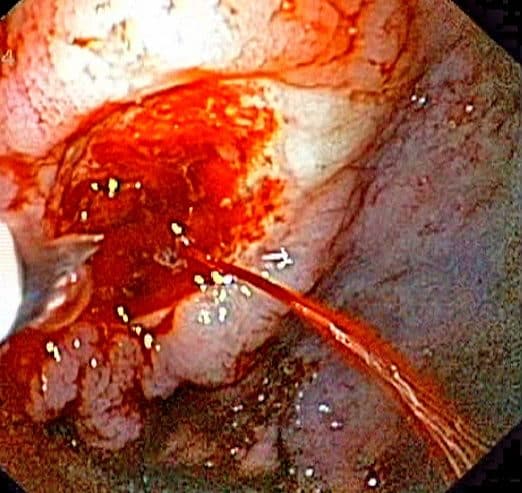

Ulcerating oesophageal or gastric malignancies (Fig. 2) can first present with melena, causing a gradual flow of blood that may present prior to any other cancer-associated symptoms.

In the assessment of any patient with melena, it is important to enquire about dysphagia, dyspepsia, weight loss, and relevant family history, potentially suggestive a diagnosis of malignancy.

Figure 2 – A gastric malignancy, first presenting as melena